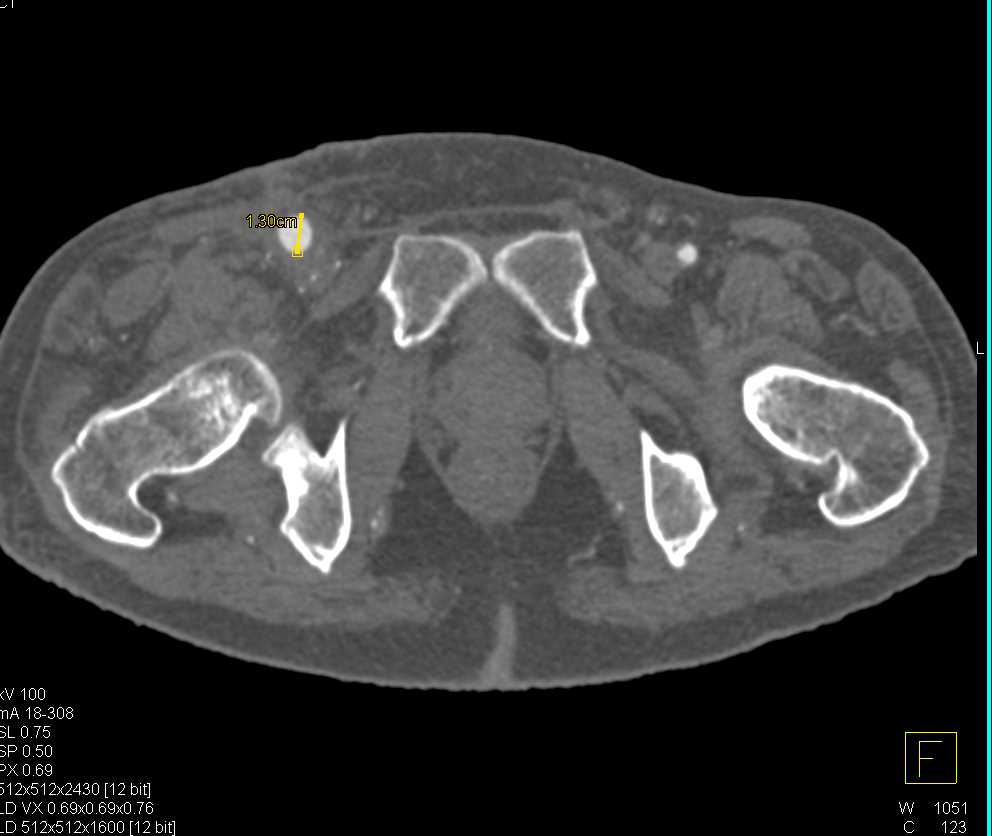

Splenic Artery Aneurysms